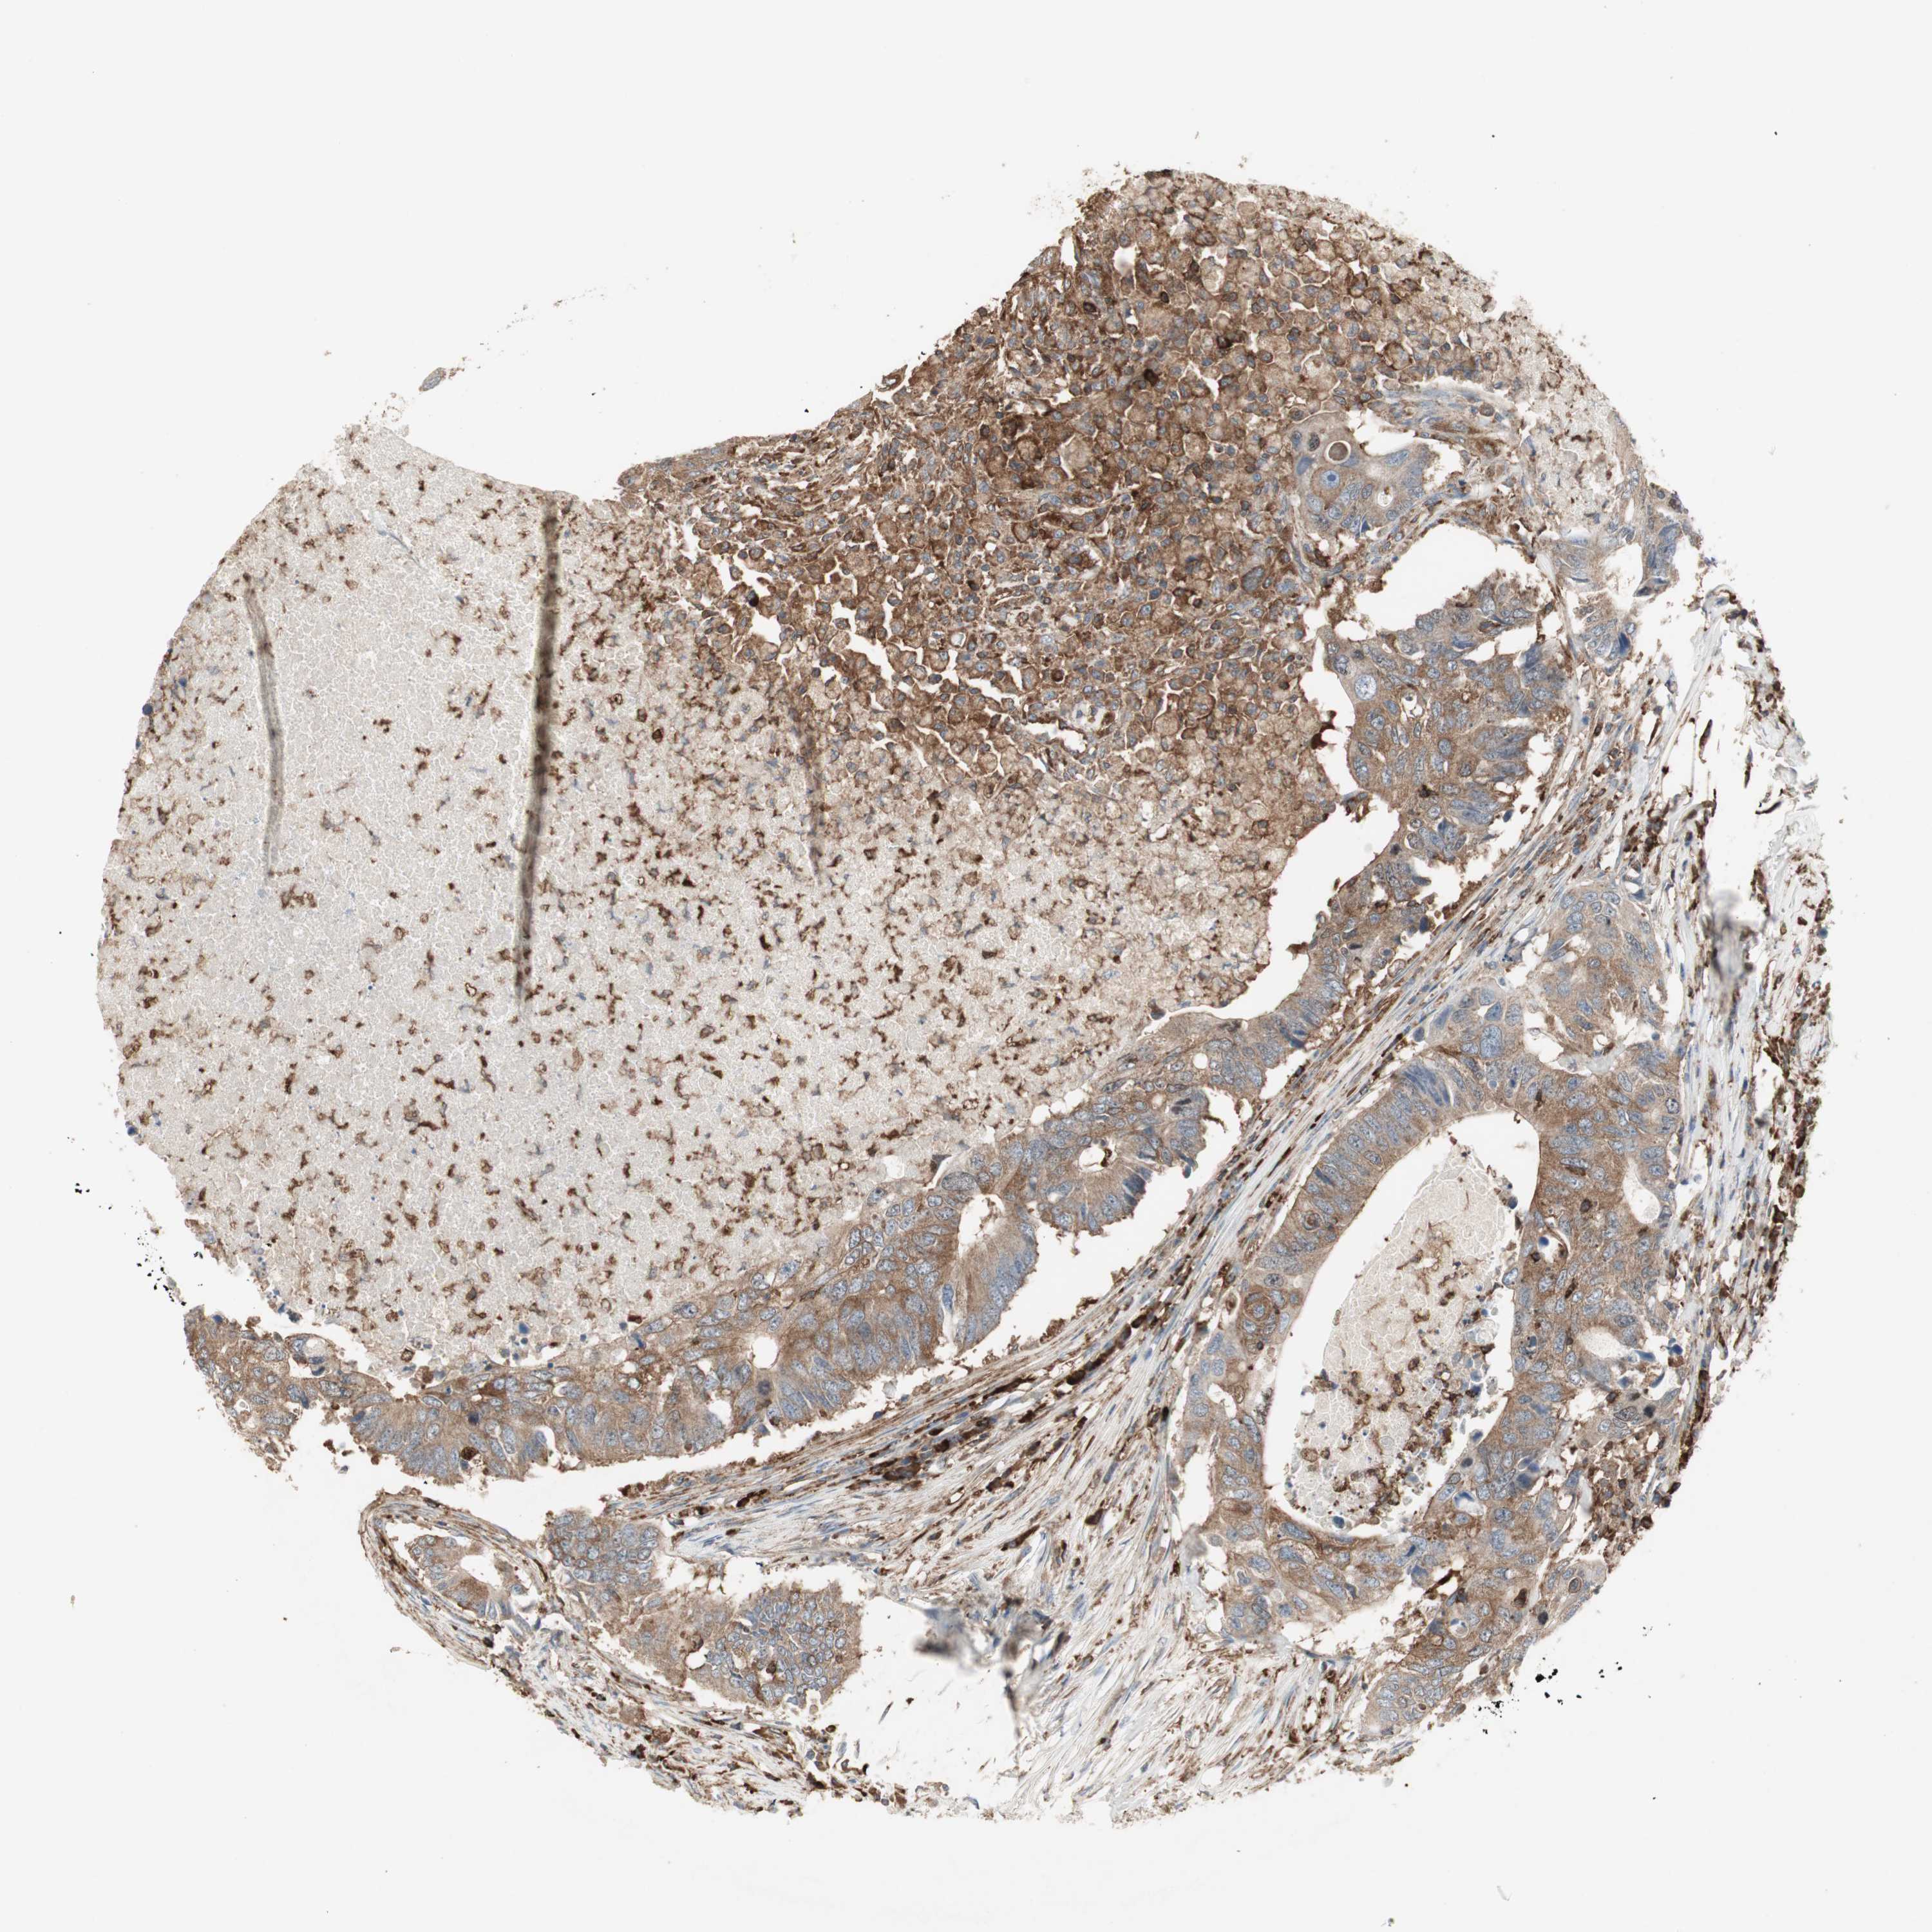

CANCER COLORECTAL CANCER Show tissue menu

Colorectal cancer

Human cancer

Colon adenocarcinoma

Rectum adenocarcinoma